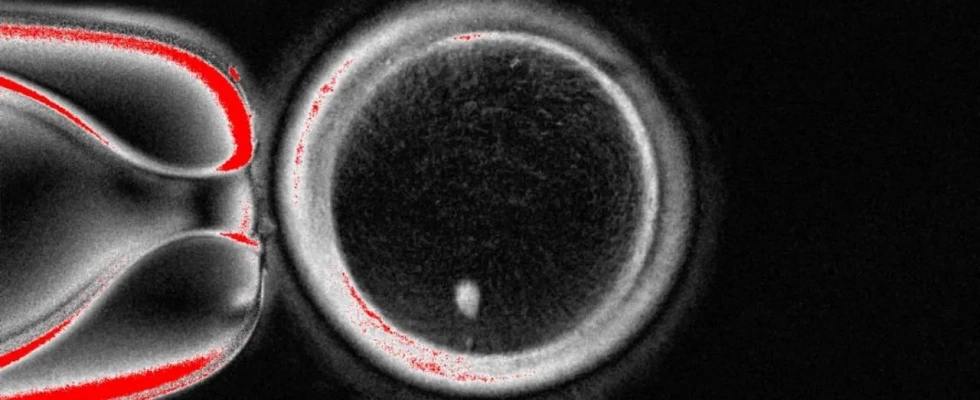

Un equipo de la OHSU (Oregon Health & Science University, EE UU), liderado por Shoukhrat Mitalipov, ha desarrollado una técnica experimental denominada mitomeiosis. El procedimiento consiste en transferir el núcleo de una célula somática —como las de la piel— a un óvulo donado sin núcleo, y provocar que divida su carga genética, imitando los pasos de la meiosis natural.

El experimento permitió obtener 82 óvulos funcionales, que fueron fecundados con esperma humano. Un 9 % alcanzó la fase de blastocisto, correspondiente a los primeros seis días de desarrollo embrionario. Aunque ninguno se cultivó más allá de ese punto, los autores destacan que se trata de una prueba de concepto que demuestra la viabilidad de generar gametos humanos a partir de células somáticas.

El trabajo también señala importantes limitaciones. La mayoría de los embriones no progresaron y se detectaron anomalías genéticas, lo que obliga a realizar más estudios antes de plantear posibles aplicaciones clínicas.

“Todavía no hemos conseguido que los 23 cromosomas correctos se eliminen al formar el corpúsculo polar”, explica Martí. “Esto ocurre porque, al introducir el núcleo de una célula somática en el óvulo, los cromosomas homólogos no se alinean correctamente en el nuevo huso acromático. Al no producirse ese emparejamiento, la separación durante la división genera muchas alteraciones genéticas (aneuploidías) que impiden el desarrollo normal del embrión”, añade.